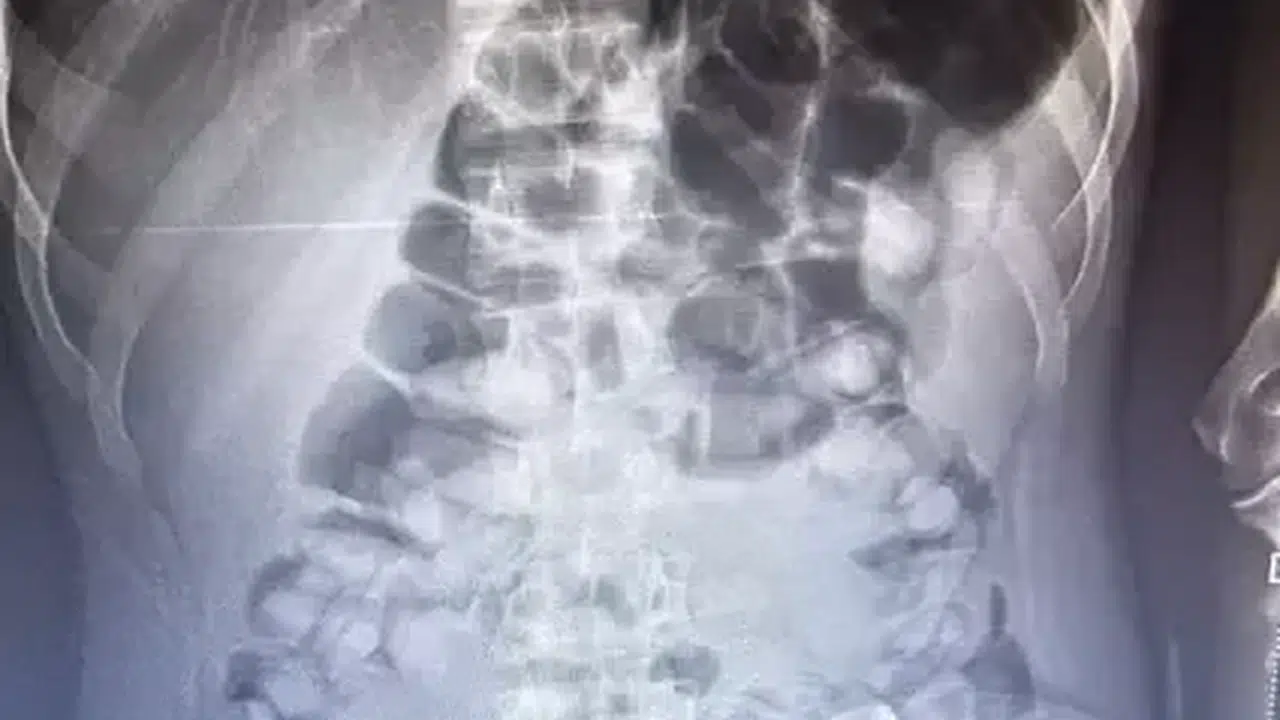

ERZURUM'da, yolcu otobüsünde şüphe üzerine hastanede röntgeni çekilen yolcunun midesinde Afyon sakızı, tespit edildi. Yolcu, midesindeki 1 kilo 134 gram Afyon sakızını doğal yollarla çıkardı.

İl Emniyet Müdürlüğü Narkotik Suçlarla Mücadele Şube Müdürlüğü ekipleri, bir yolcu otobüsünde yaptığı denetimde, durumundan şüphelendiği yolcuyu hastaneye götürdü. Burada rdöntgeni çekilen yolcunun midesinde uyuşturucu tespit edildi. İlaç verilen yolcu, 1 kilo 134 gram Afyon sakızını doğal yollarla çıkardı.